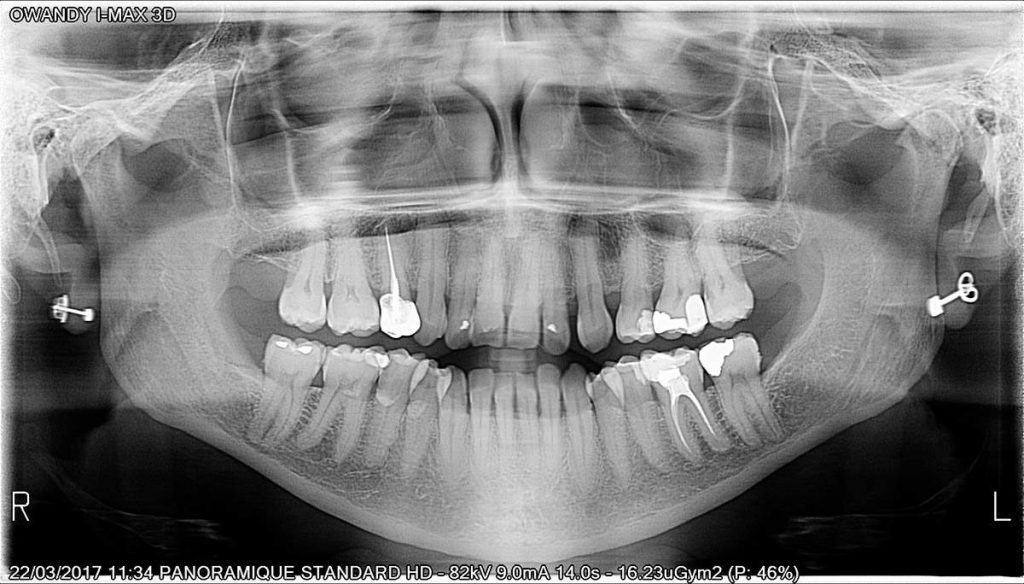

Calidad de imagen excepcional

I MAX-3D